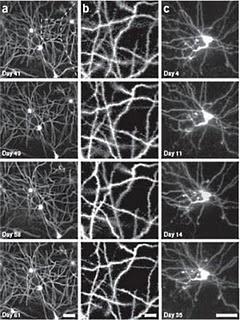

Primero se insertan en la región deseada, con anestesia, finos y pequeños tubos, del tamaño de un grano de arroz. Cuando se quieren visualizar las células, se inserta un microendoscopio en un tubo, que termina en cristal transparente. Los tubos permiten volver una y otra vez a la misma zona del cerebro y observar las neuronas con un detalle que ninguna otra técnica permite. El microendoscopio funciona con luz láser.

Debido a que la microscopía óptica sólo puede penetrar la capa más superficial de los tejidos, toda región cerebral a más profundidad de 700 micras resulta inalcanzable con técnicas tradicionales. Con el nuevo método se pueden tomar imágenes durante mucho tiempo sin causar daño, explica Juergen Jung, director de operaciones en el laboratorio de Schnitzer.